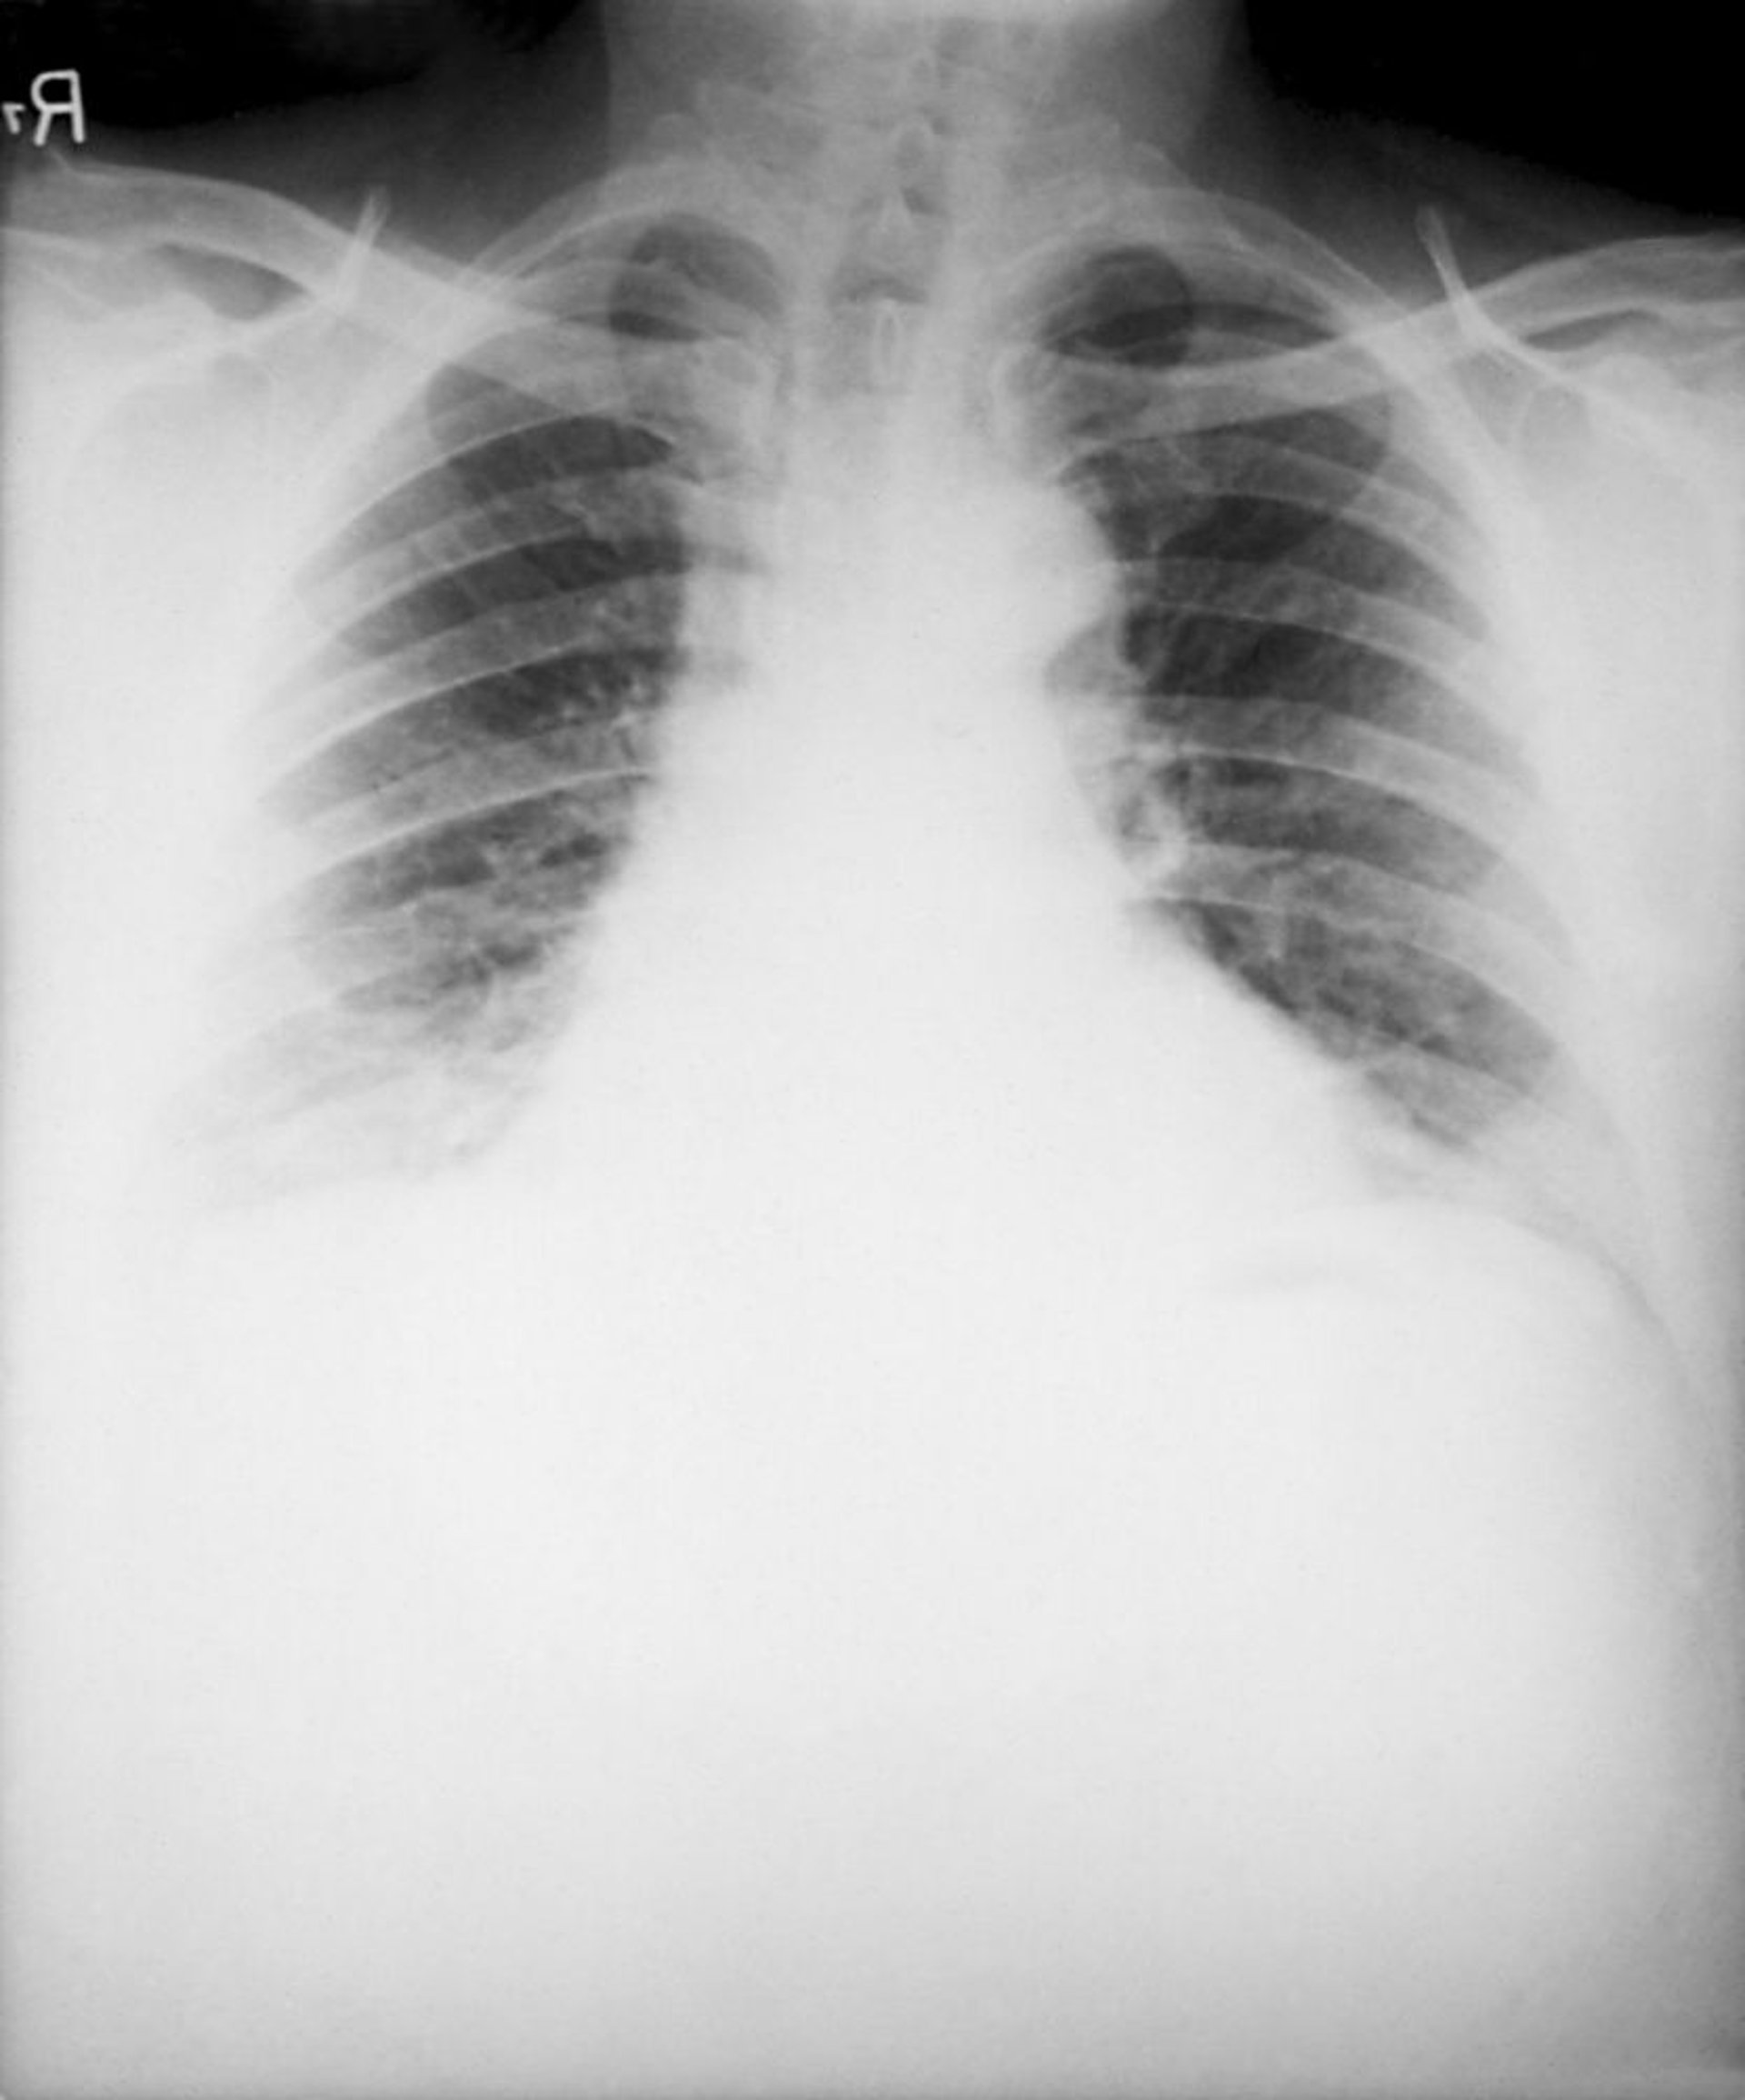

Anthrax (Inhalation)

Typical findings of inhalation anthrax on chest radiograph include a widened mediastinum caused by hemorrhagic necrotizing mediastinal lymphadenitis and bilateral pleural effusions. Pneumonic infiltrates are uncommon.

Image courtesy of the Public Health Image Library of the Centers for Disease Control and Prevention.